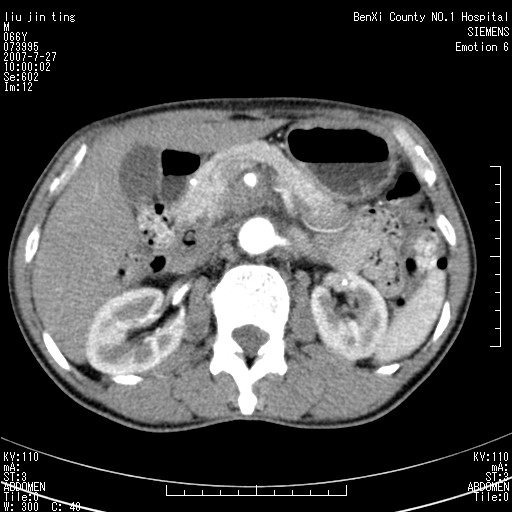

沿着肠系膜上动脉呈匍匐性生长的软组织肿块,形态不规则,包绕肠系膜上动脉,呈明显强化,考虑来源于肠系膜的恶性肿瘤

沿着肠系膜上动脉呈匍匐性生长的软组织肿块,形态不规则,包绕肠系膜上动脉,呈轻-中度强化,考虑来源于肠系膜的恶性肿瘤。

钩突是正常的,只见腹膜后淋巴结的肿大,考虑淋巴瘤或转移可能。

腹膜后占位性病变,首先考虑肿大淋巴结。

考虑为腹膜后恶性纤维组织细胞瘤。